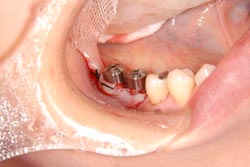

![]() インプラントの全貌 こちらを埋入していきます。 1次ope、2次opeに分かれています。 1次opeはインプラント埋入ope、2次opeは歯肉の状態をきれいにするために行うopeです。 |

![]() 2次ope終了時このまま3週間〜1ヶ月まちます。 |

![]() 2次opeがおわり、1ヶ月程たって歯肉の状態がよくなっています。 |